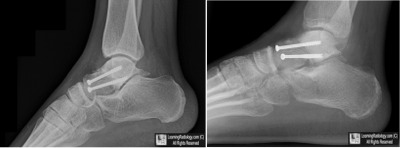

Case of the Week 536

What is the most likely diagnosis?

• 48 year-old with injury 6 months earlier

Lateral Radiographs of the Ankle

5. Avascular Necrosis of Talus

Avascular Necrosis of Talus

• The vascular supply to the talus consists of relatively small vessels combined with poor collateral circulation which predispose the talus to avascular necrosis when there is a disturbance of its blood supply

• The talus is also covered by a large percentage of articular cartilage which is not penetrated by blood vessels